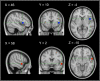

Self-voice attribution can become difficult when voice characteristics are ambiguous, but functional magnetic resonance imaging (fMRI) investigations of such ambiguity are sparse. We utilized voice-morphing (self-other) to manipulate (un-)certainty in self-voice attribution in a button-press paradigm. This allowed investigating how levels of self-voice certainty alter brain activation in brain regions monitoring voice identity and unexpected changes in voice playback quality. FMRI results confirmed a self-voice suppression effect in the right anterior superior temporal gyrus (aSTG) when self-voice attribution was unambiguous. Although the right inferior frontal gyrus (IFG) was more active during a self-generated compared to a passively heard voice, the putative role of this region in detecting unexpected self-voice changes during the action was demonstrated only when hearing the voice of another speaker and not when attribution was uncertain. Further research on the link between right aSTG and IFG is required and may establish a threshold monitoring voice identity in action. The current results have implications for a better understanding of the altered experience of self-voice feedback in auditory verbal hallucinations.